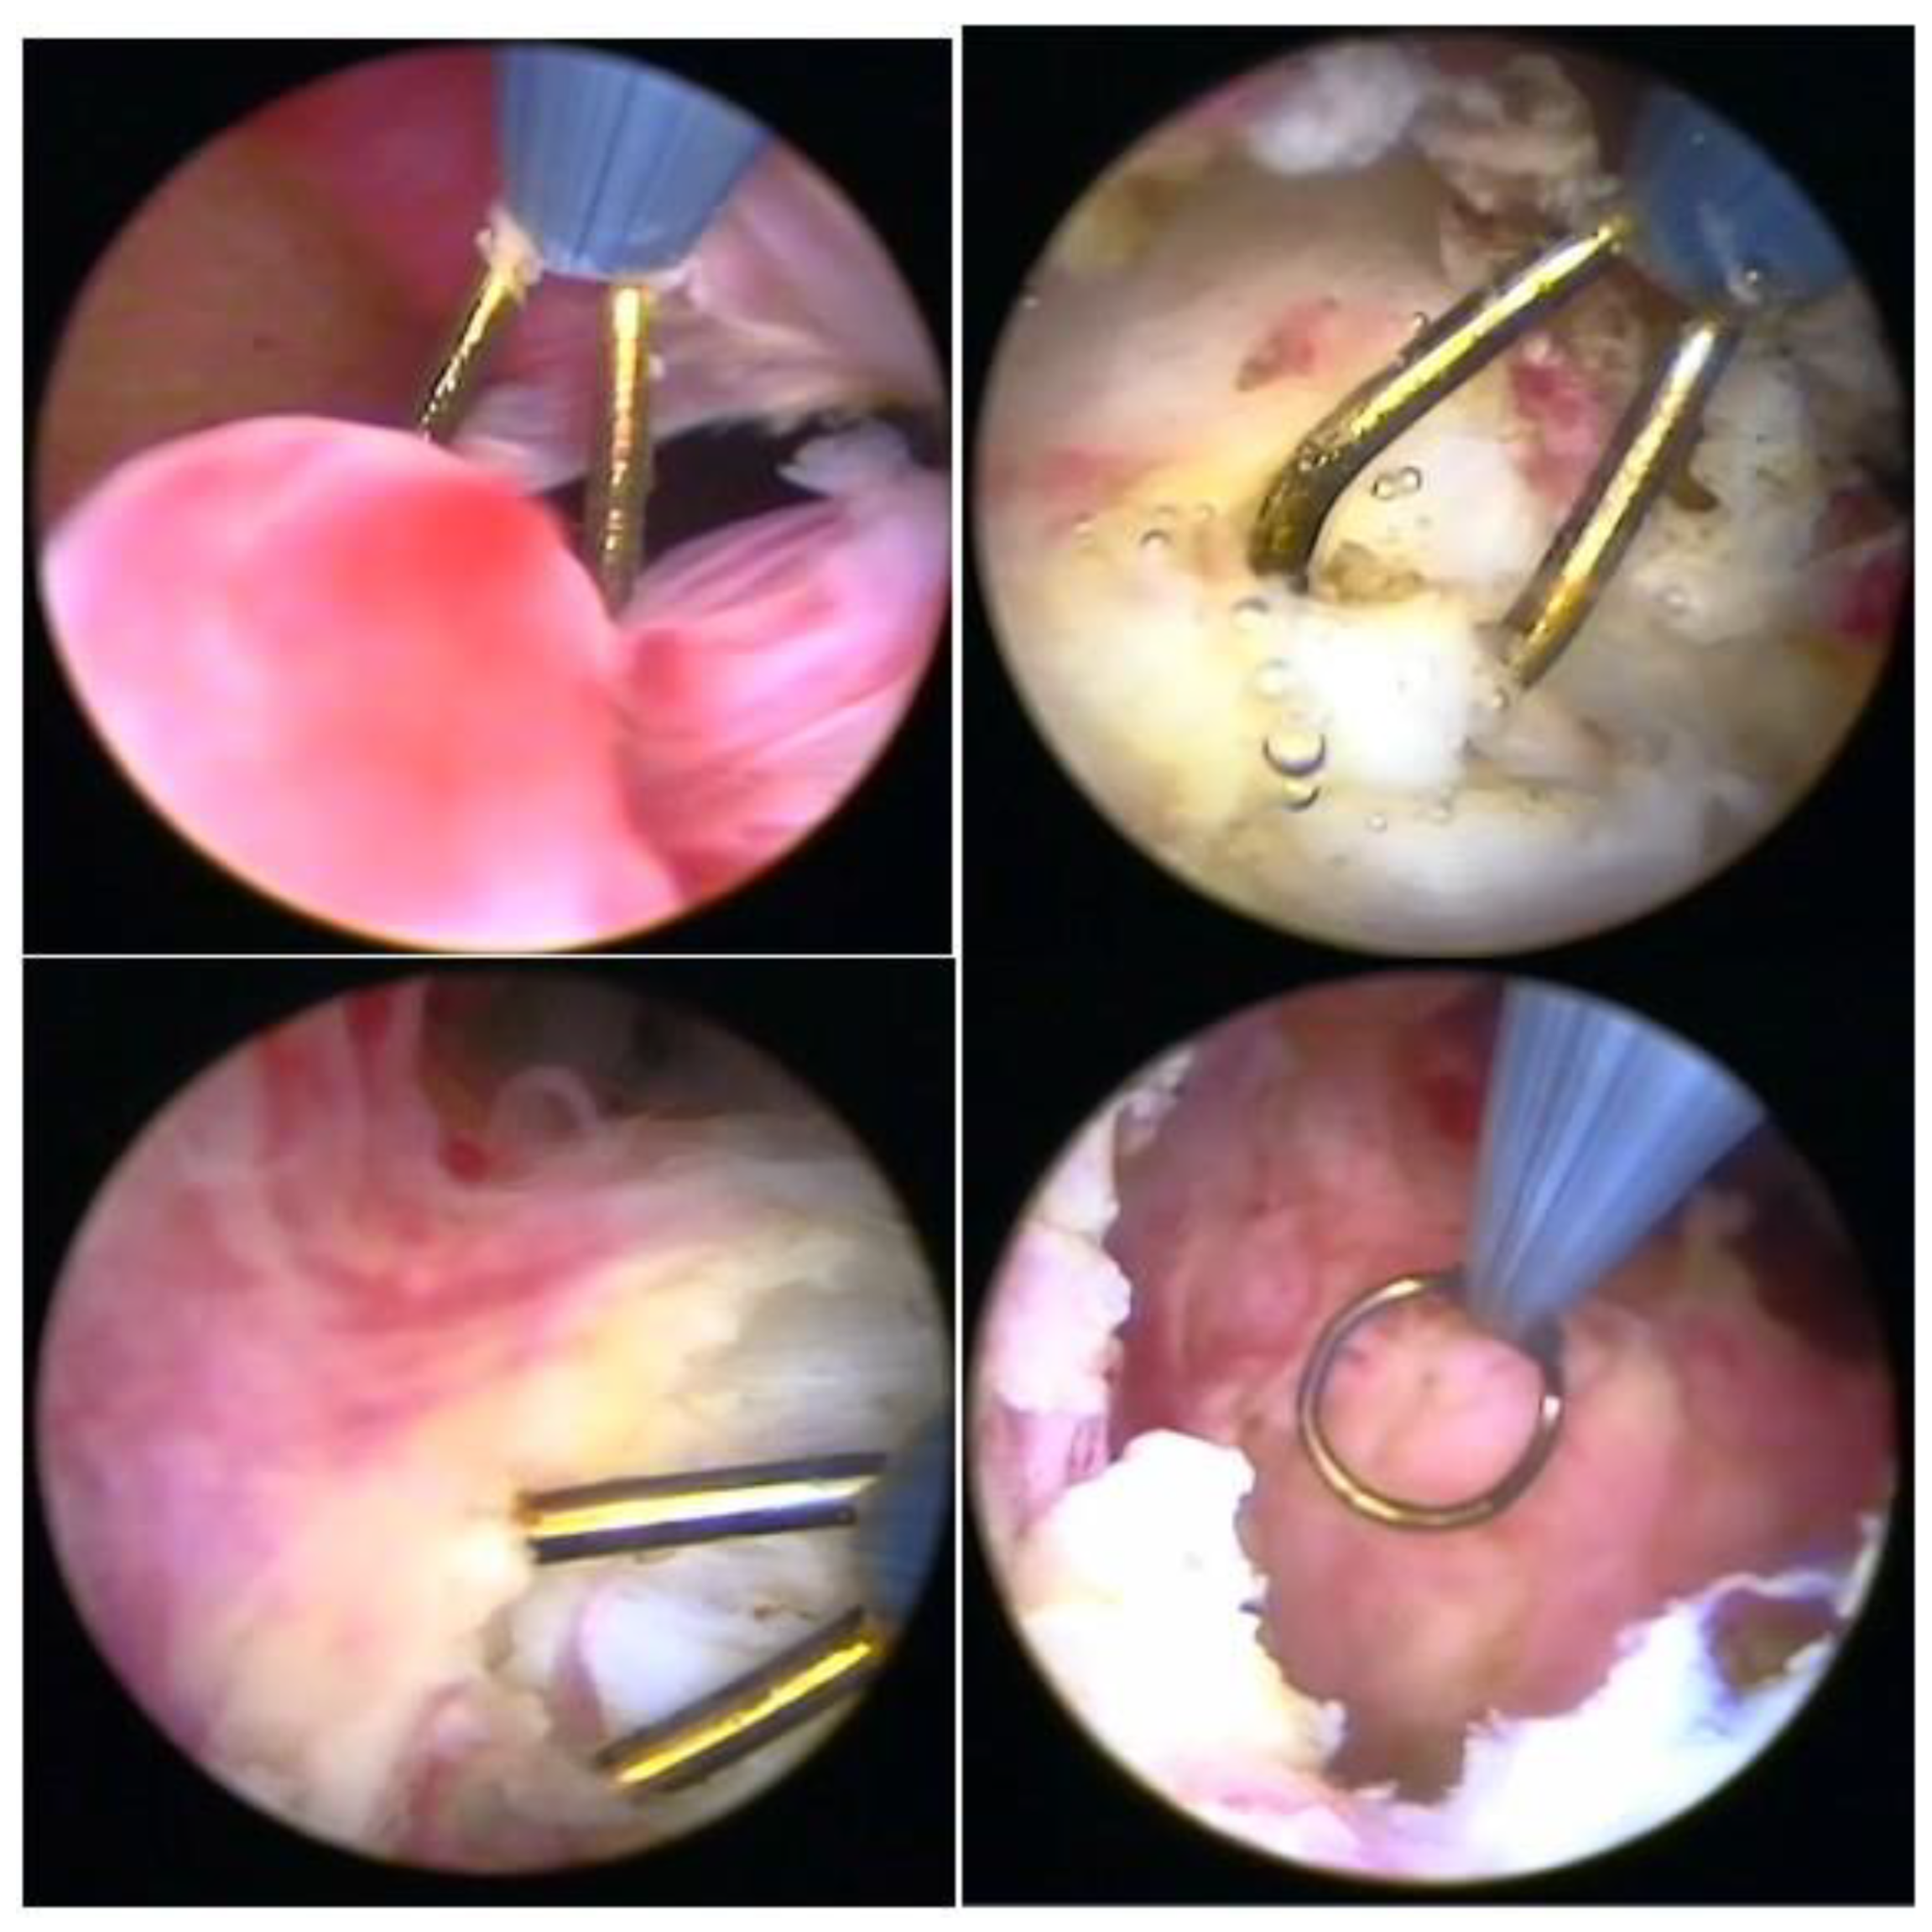

The technique with the resectoscope, regardless of the type of energy, is the same, with planned loop movements always in the fundus–cervical direction, with the angulation of the resectoscope axis to define the degree of resection depth. These two movements have to be thought out and prepared before activating the energy so that only the myoma is resected, avoiding resection of the myometrium and the risk of perforation, and so that the penetration of the cut is as desired, without risk (Figure 9).

3.4. Slicing Technique

The principle of the slicing or slicing technique is the partial and progressive removal of the myoma, in fragments, starting at its surface and gradually working towards its base. Slices of myoma are removed with the semicircle loop in the mono or bipolar resectoscope, moving it energized, from the fundus to the cervix. The distension medium is different according to the type of energy; with monopolar energy, non-electrolytic media are used, which are 1.5% glycine, mannitol, and mannitol/sorbitol, while, with bipolar energy, the electrolytic media, physiological solute 0.9%, and ringer lactate are used [27] (Figure 10).

3.5. Morcellator Technique (Hysteroscopic Mechanical Tissue Removal)

Hysteroscopic Tissue Removal Systems (TRS) perform fragmentation and suction of endometrial pathology, such as polyps and fibroids. There are three main brands currently available on the market (e.g., Myosure, Truclear, and Symphion) and they are mainly used for types 0 and 1 intrauterine leiomyomas. A rapidly rotating blade resects small portions of the fibroid, and these are suctioned into a tissue trap for pathologic evaluation. This technique alleviates the need for removal of fibroid “chips” from the cavity and it has been shown to be faster for trainees.

Hysteroscopic tissue removal systems introduced an efficient, easy-to-use tool for hysteroscopic myomectomy. However, there are limitations, such as the high cost of the disposable element, as well as the difficulty resecting fundal fibroids and deep type 2 fibroids. In addition, dense and calcified fibroids can be very challenging to resect with these devices. One study showed that switching to a resectoscope in these cases allowed for finalization of the procedure [28]. However, another meta-analysis showed statistically significant improvement in complete resection of pathology when tissue extraction devices were used [29]. The surgeon should tactfully choose the best tool based on the pathology, its size, location, the patient’s goals, and the surgeon’s expertise.

Morcellators have expanded their use, with good acceptance, especially by those who are starting hysteroscopic surgery, due to practicality of use, short learning time, and non-use of energy (only mechanics), with good performance in the treatment of intracavitary lesions. Its limits are more intramural lesions, and lesions in cornual and fundic regions (Figure 11).

Figure 9. Correlation with hysteroscope angulation and tissue depth.

Figure 10. Slicing technique.

Figure 11. Morcellator technique—hysteroscopic mechanical tissue removal.